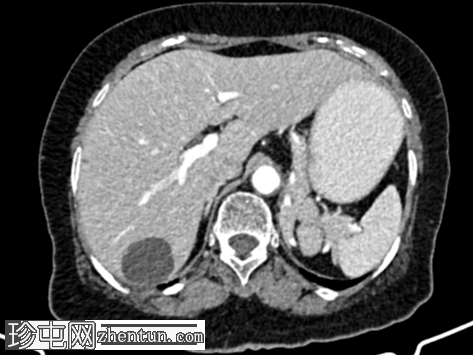

CT

扫描

1.jpg

轴位

平扫

左肾及左肾动脉缺如。

左侧肾上腺呈垂直方向。

肝脏 VI 段包膜下可见一个低密度、低强化的单纯性囊肿(大小为 34.4 x 33.6 x 31.1 mm)。